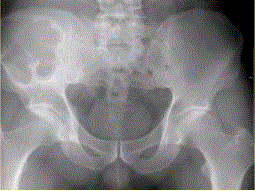

患者男,28岁,右下腹及臀部疼痛5个月余。查体:右髂骨外后侧压痛,右下腹可触及一软组织包块,质韧,固定。行骨盆正位CR、骨盆CT及MR扫描见下图。...

问题 患者男,28岁,右下腹及臀部疼痛5个月余。查体:右髂骨外后侧压痛,右下腹可触及一软组织包块,质韧,固定。行骨盆正位CR、骨盆CT及MR扫描见下图。 此病变最可能的诊断是

选项 A.骨囊肿 B.动脉瘤样骨囊肿 C.骨结核 D.骨巨细胞瘤 E.硬韧带样纤维瘤

答案 B